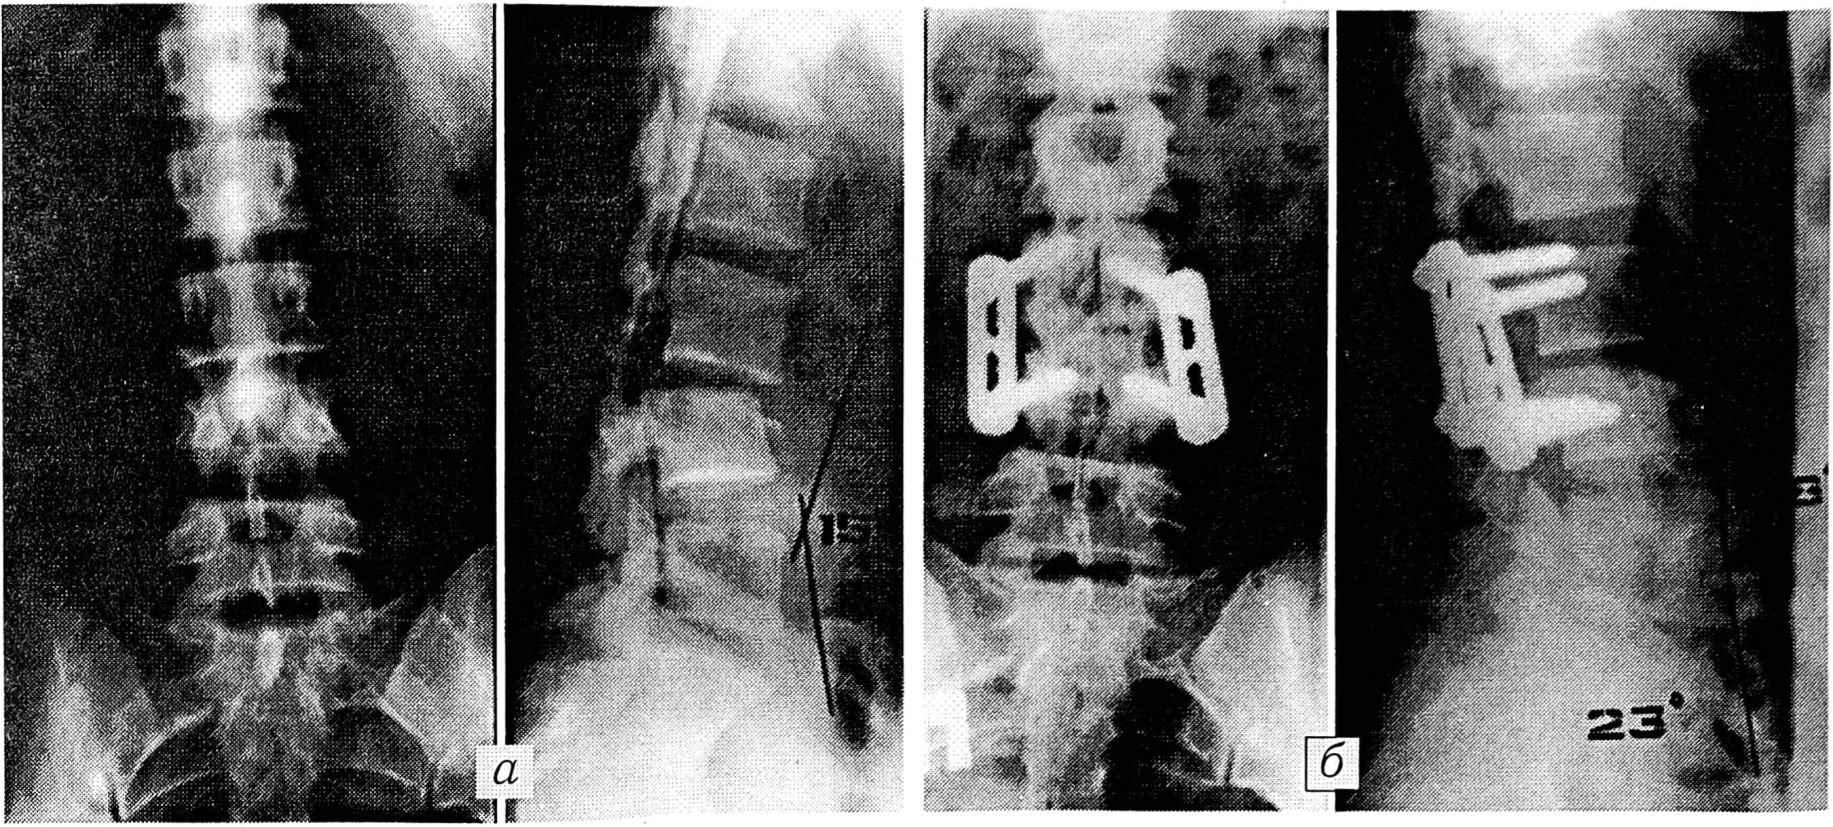

Если имелись вторичный болевой синдром или незначительная органическая неврологическая симптоматика (арефлексия, нарушение чувствительности), а при применении дополнительных методов исследования выявлялся компрессионный перелом позвонка без повреждения межпозвонкового диска и не было данных, указывающих на сдавление спинного мозга, производили фиксацию поврежденного сегмента позвоночника системой Steffee в сочетании с задним спондилодезом (спондилодез выполняли по дугам, суставным и поперечным отросткам). Аналогичная тактика была применена у больной с переломовывихом L3 позвонка без выраженной неврологической симптоматики (см. рис. 1).

Рис. 1. Больная Л.

Травма получена в результате падения с 4-го этажа. Переломовывих LЗ позвонка (а). Операция (6): фиксация LЗ-4 позвонков системой Steffee, достигнута полная репозиция.

В случаях, когда даже при минимальной неврологической симптоматике выявлялся разрыв межпозвонкового диска с выходом его в позвоночный канал и имелось сдавление дурального мешка на 1/3 диаметра (поврежденным диском или фрагментами сломанного тела позвонка), производили из заднебокового доступа с помощью специального инструментария фенестрацию и удаление поврежденного диска и замыкательных пластинок, выполняли межтеловой спондилодез аутотрансплантатом (из резецированного ребра или из крыла подвздошной кости), а позвоночник фиксировали системой Steffee в сочетании с задним спондилодезом (см. рис. 2).

Рис. 2. Больная М.

Травма получена в результате падения с параплана с высоты 5 м. Перелом L1 позвонка, сопровождающийся сдавлением дурального мешка до 1/3 диаметра (а). Неврологически: оживление сухожильных рефлексов, выражены симптомы натяжения. Операция (б): фенестрация диска Т12—L1 с удалением его, фиксация Т12 —L2 позвонков системой Steffee, межтеловой спондилодез Т12—L1 аутотрансплантатом из резецированного XII ребра.